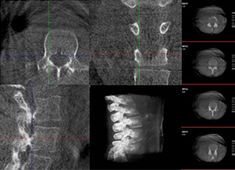

術中三維CT如何輔助手術機器人完成手術導航

手術機器人對術中配準的要求較高,僅依靠其自身的導航定位功能還遠遠不夠,需要結合術中三維CT影像來提高導航精準度。術中三維CT是如何輔助手術機器人完成手術導航的?下面以術中三維移動C臂(PLX C7600)輔助脊柱外科手術...